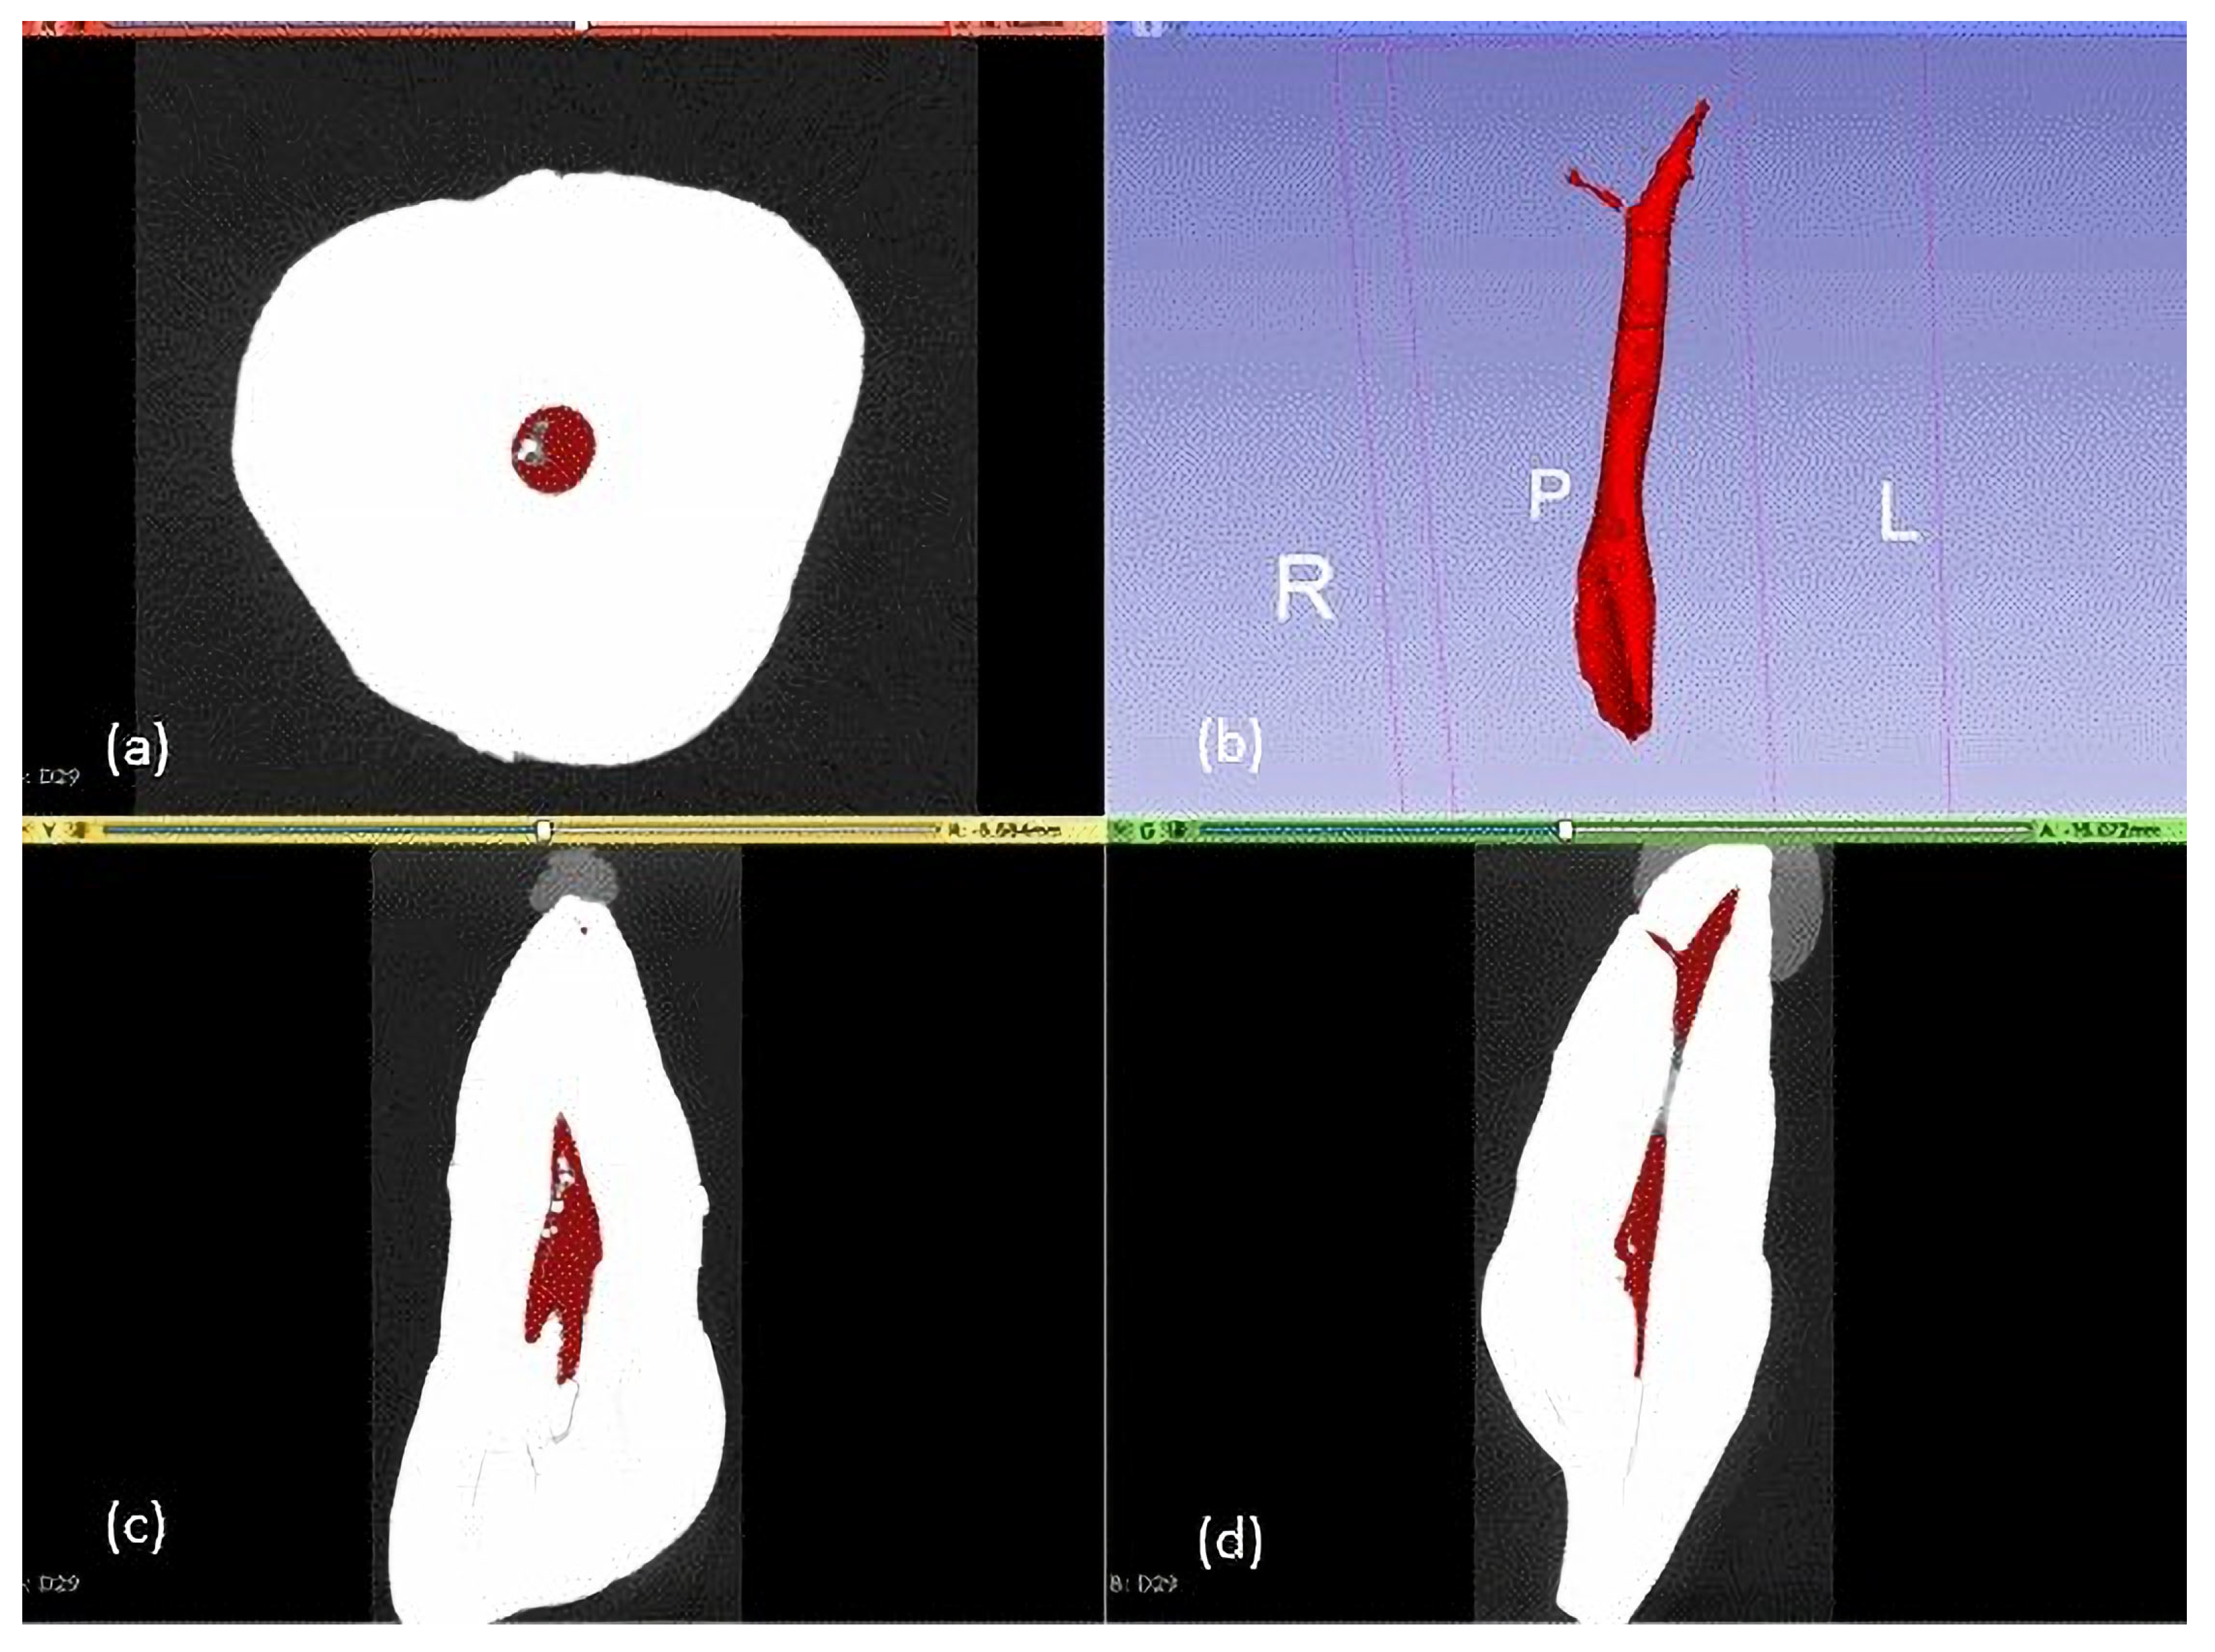

Figure 2.

Micro-CT image of a specimen showing pulp volume measurement in three planes: (a) axial plane; (c) coronal plane; (d) sagittal plane; (b) 3D reconstruction of pulp volume, where R, P, L, stands for Right, Pulp, Left.